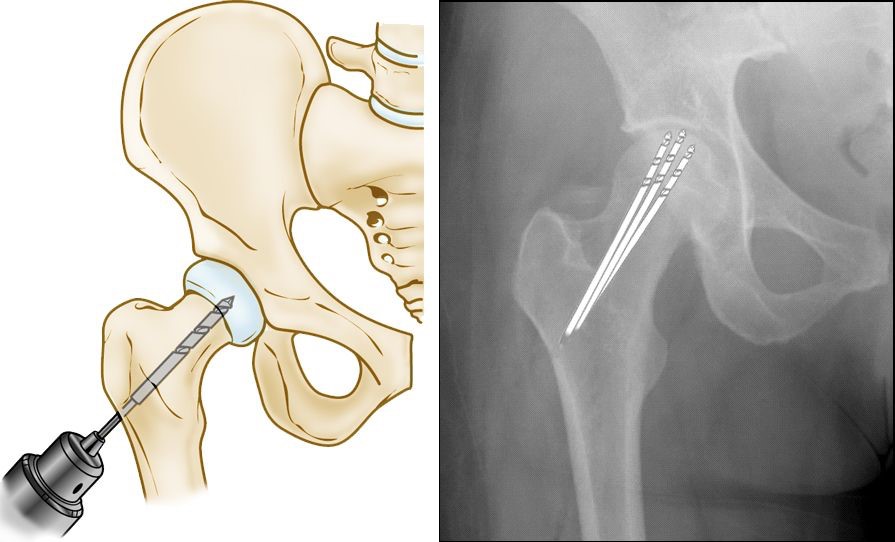

This procedure involves drilling one larger hole or several smaller holes into the femoral head to relieve pressure in the bone and create channels for new blood vessels to nourish the affected areas of the hip. When osteonecrosis of the hip is diagnosed early, core decompression is sometimes successful in preventing collapse of the femoral head and the development of arthritis.

(Left) Illustration of core decompression. (Right) In this x-ray, the drill lines show the pathway of the small drill holes used in the procedure.